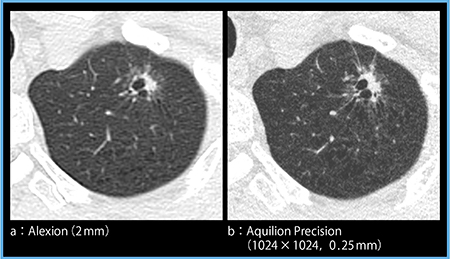

症例4は,2mmスライス厚の画像(図4 a)では辺縁にすりガラス状陰影があり腺癌が疑われるが,気腫があるために境界がわかりにくい部分がある。一方,Aquilion Precision(1024×1024マトリックス,0.25mmスライス厚)の画像(図4 b)では,気腫状の部分の間にすりガラス状陰影が明瞭な境界を持って広がっていることが確認でき,腺癌であると自信を持って診断できる。0.25mmスライス厚の画像では,充実性部分に向かって気腫性病変が変形して引っ張られている状態まで把握できる。このような所見から,充実性の部分は線維化を伴っていると考えられ,全体として腺癌の所見と矛盾しないことがわかる。

図4 症例4:肺腺癌(part solid nodule)